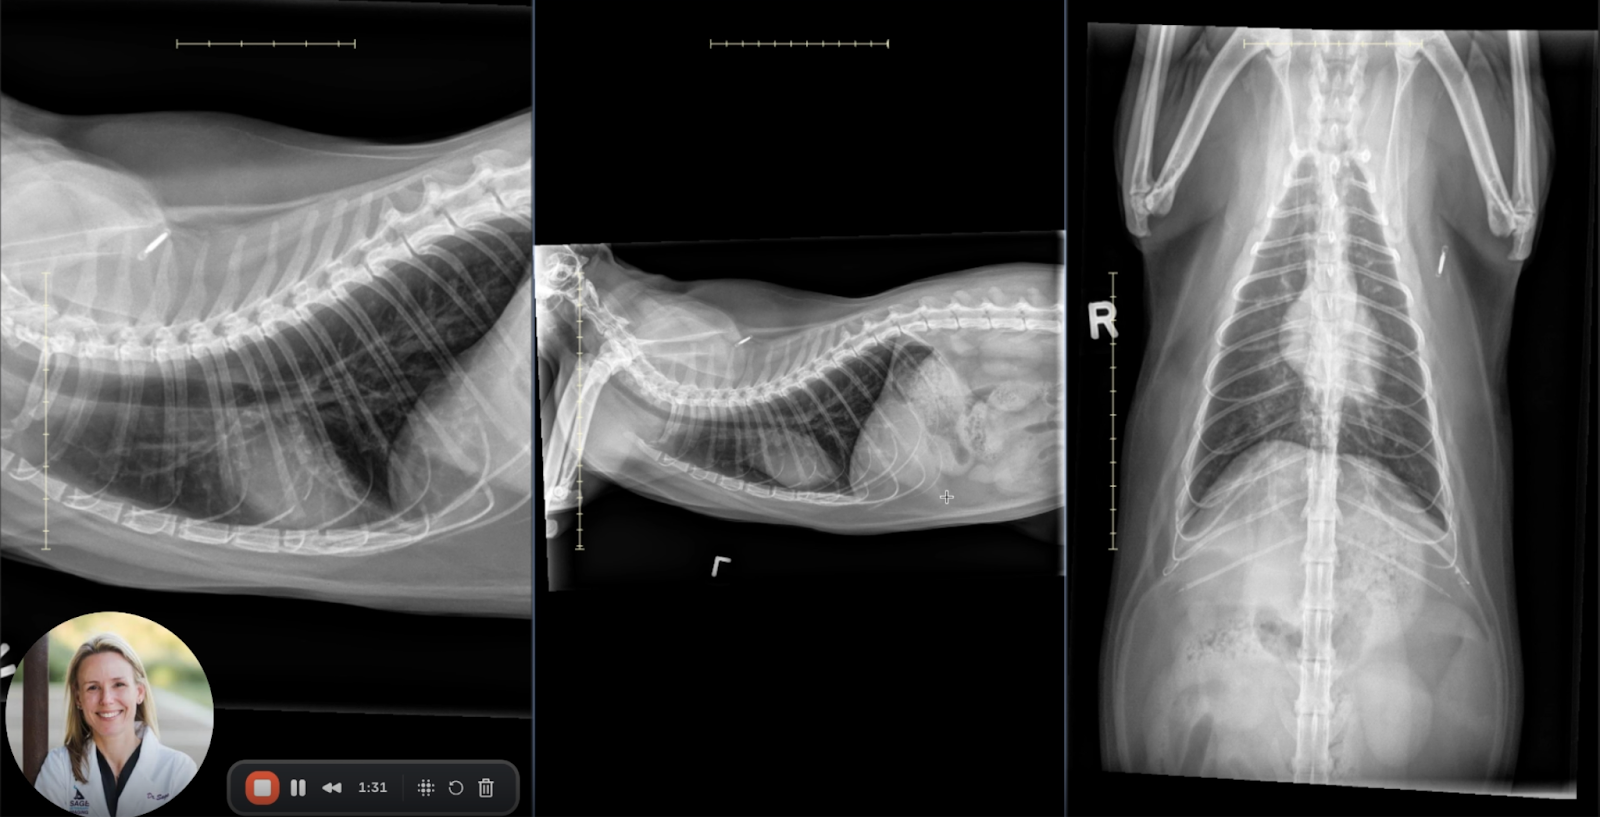

Image 1: Right Lateral View

• Cardiac Silhouette: Normal in size and shape with no radiographic signs of cardiomegaly, pulmonary venous congestion, or right heart enlargement.

• Pulmonary Parenchyma: A generalized bronchial pattern is evident throughout both lung fields. Bronchial wall thickening is pronounced, producing characteristic “railroad track” signs in longitudinal sections and “donut ring” appearances in transverse sections—radiographic hallmarks of chronic bronchial inflammation.

• Pulmonary Inflation: Notable hyperinflation is present. The diaphragm appears flattened, and intercostal spaces are widened, indicating expiratory air trapping and increased lung volume.

• Tracheal Morphology: There is dilation of the intrathoracic trachea relative to the cervical portion, a finding consistent with obstructive lower airway disease and reduced expiratory airflow.